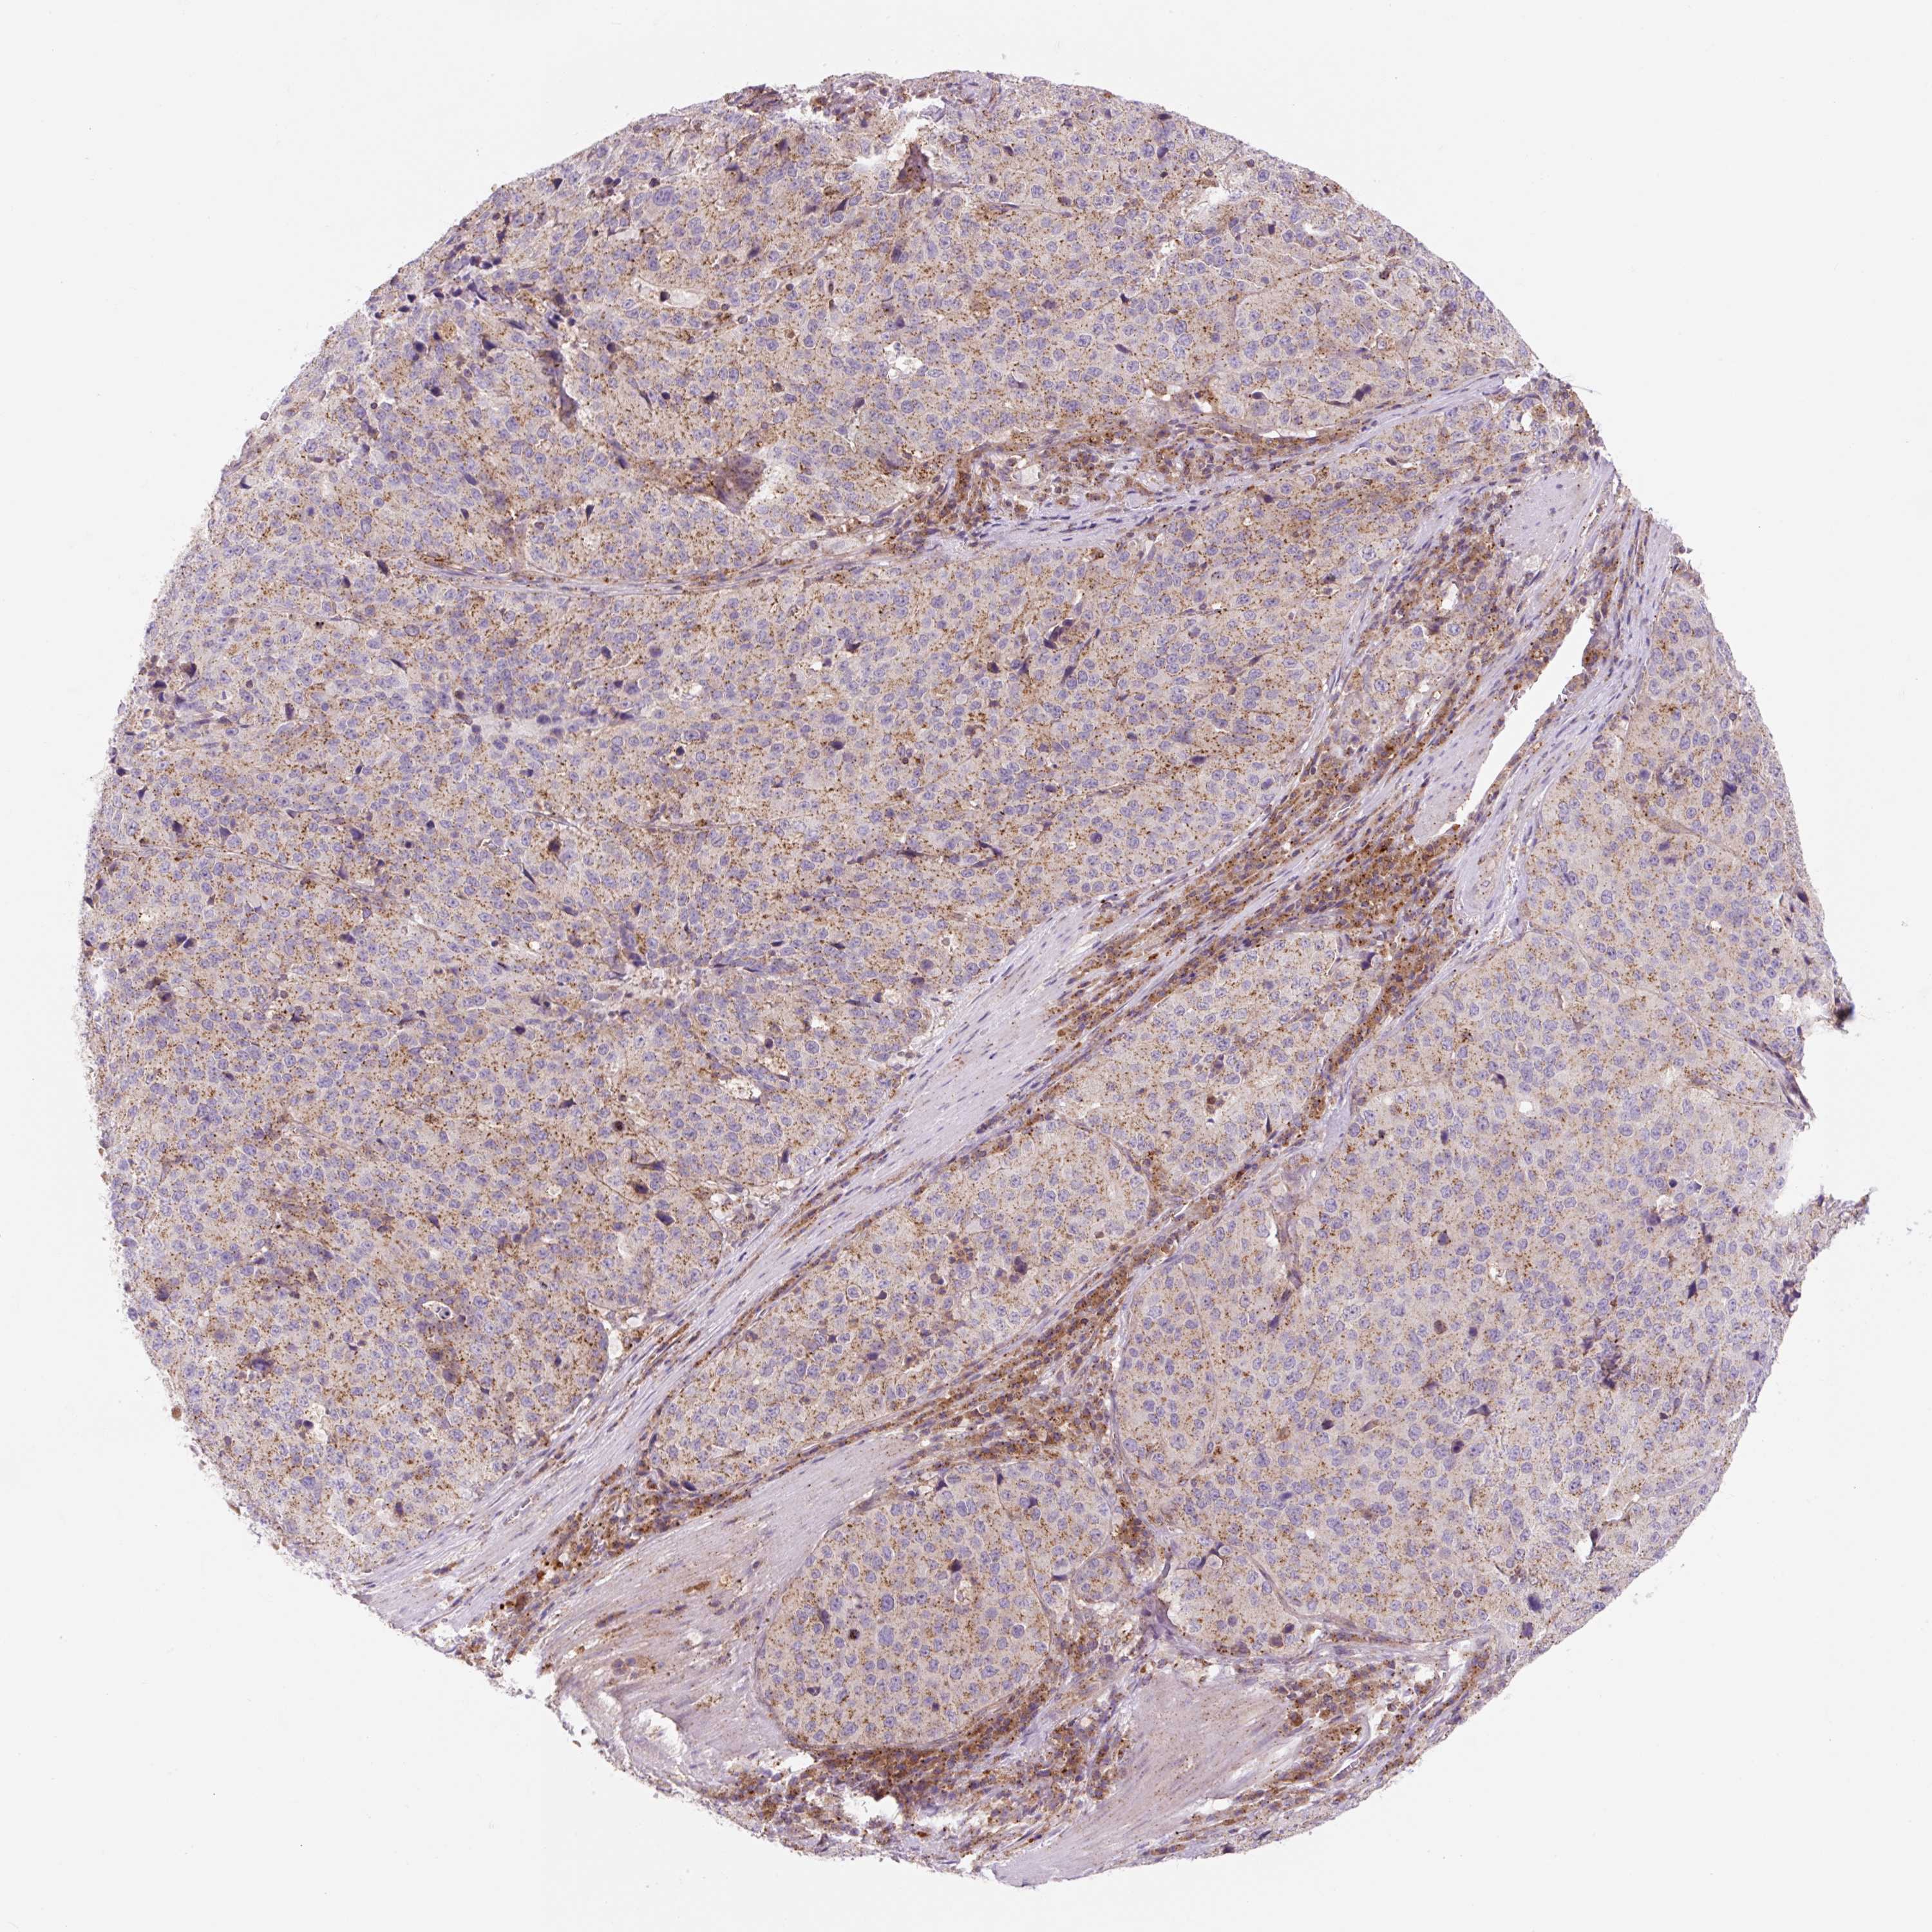

STOMACH CANCER - Protein expressioni

A mouse-over function shows sample information and annotation data. Click on an image to view it in a full screen mode. Samples can be filtered based on level of antibody staining by selecting one or several of the following categories: high, medium, low and not detected. The assay and annotation is described here.

Note that samples used for immunohistochemistry by the Human Protein Atlas do not correspond to samples in the TCGA dataset.

Antibody stainingi

Antibody staining in the annotated cell types in the current human tissue is reported as not detected, low, medium, or high, based on conventional immunohistochemistry profiling in selected tissues. This score is based on the combination of the staining intensity and fraction of stained cells.

Each image is clickable and will lead to virtual microscopy that enables deeper exploration of all samples and also displays staining intensity scores, fraction scores and subcellular localization as well as patient and tissue information for each sample.

Antibody CAB018751

Antibody CAB034411

Staining

High

Medium

Low

Not detected

Intensity

Strong

Moderate

Weak

Negative

Quantity

>75%

75%-25%

<25%

None

Location

Nuclear

Cytoplasmic/membranous

Cytoplasmic/membranous,nuclear

Adenocarcinoma, NOS